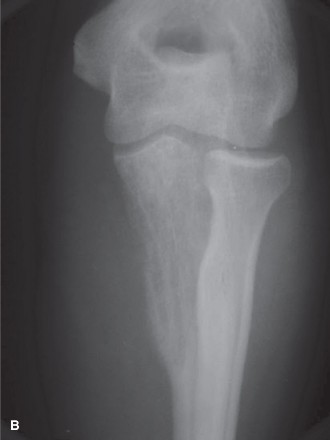

Long Bones

- Diaphyseal Involvement: ES frequently involves the diaphysis or metadiaphysis, often leading to significant cortical destruction and soft tissue extension. The peritumoral edema and reactive zone are extensive, requiring wide margins that may necessitate resection of a substantial segment of the bone.

This image potentially depicts a radiographic representation of a Ewing sarcoma in a long bone, highlighting the typical diaphyseal involvement and periosteal reaction.